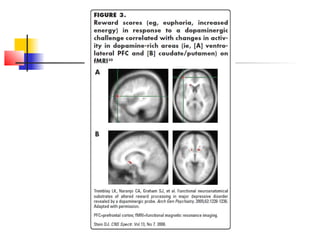

HPA axis and

 Stress  Amygdala

  increse dopamine in Prefrontal Cortext and Ventral Straitum

  altering striatal levels of BDNF.

 Acute irritable

 Chronic anhedonia

Pharmacol Biochem Behav 2002;73:147-58.

Prefrontal Cortext and Ventral

Straitum